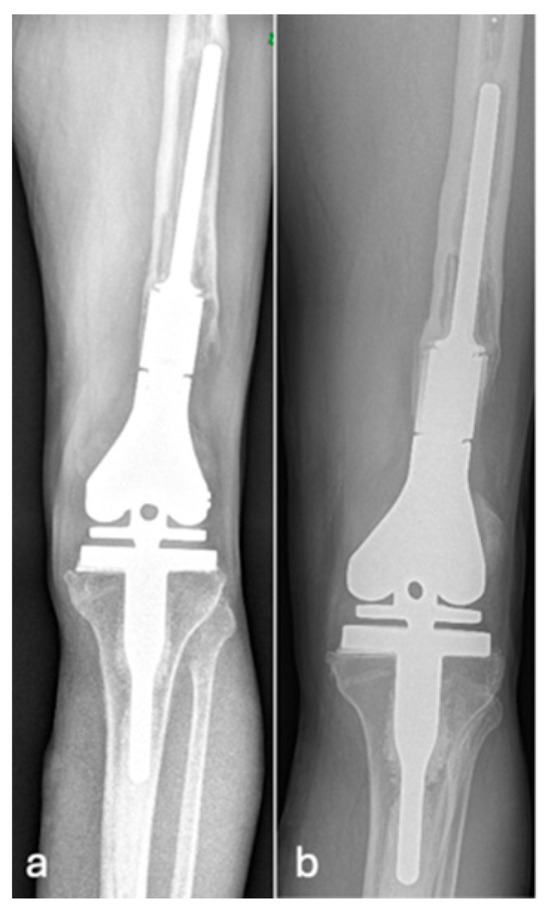

| Grade of loosening | |

| Grade 2 | 5 (17.9) |

| Grade 3 | 16 (57.1) |

| Grade 4 | 2 (7.1) |

| Grade 5 | 1 (3.6) |

| Grade 6 | 4 (14.3) |